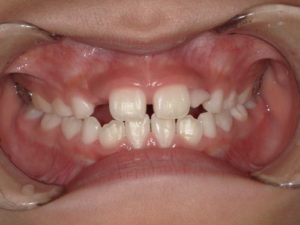

前歯2本が反対咬合 7歳

| 主訴 | 下の前歯が上の前歯より前に出てきた。 |

| 診断名 | 前歯の反対咬合 |

| 年齢・性別 | 7歳、男の子。 |

下の前歯が生え変わり、上の前歯が生え変わったと思ったら反対咬合になってしまっていました。

これだけ嚙みこんでいると、自然に治る気がしません。

この子の場合は、骨格的に下あごが大きいとかではなく、たまたま上の前歯が内側に倒れて生えてしまっただけなので、上の前歯を裏から前に押してあげれば良いだけです。

治療前